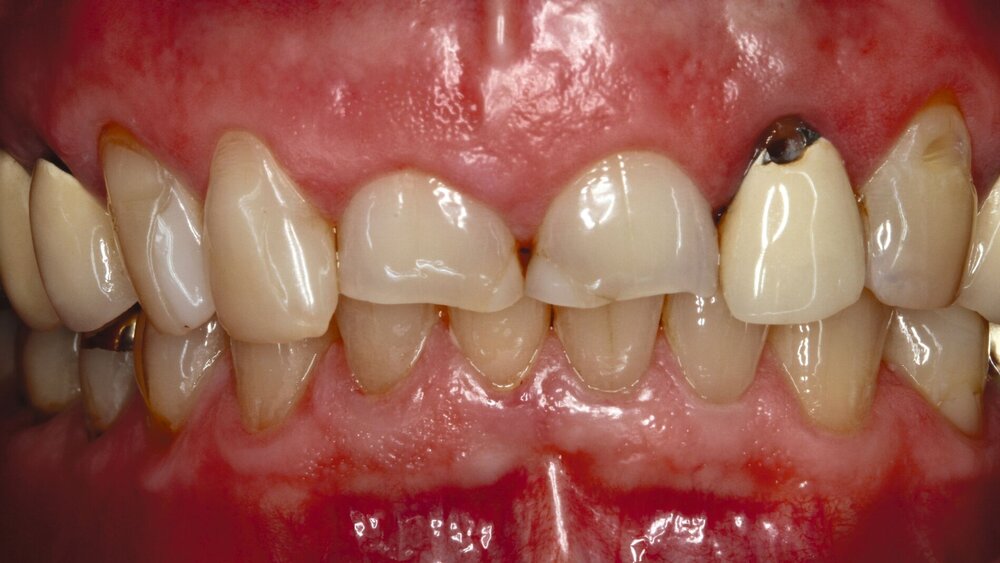

Die dentale Ausgangssituation zeigte im Seitenzahnbereich ein suffizient konservierend und prothetisch versorgtes Gebiss der zweiten Dentition sowie im Frontzahnbereich nicht kariogene Zahnhartsubstanzverluste und eine defekte Krone mit Sekundärkaries (Abbildungen 1 und 2).

Zur Verbesserung der Ästhetik und des Wohlbefindens des Patienten standen die Harmonisierung der Lachlinie und des Frontzahnbogens sowie Farb- und Formkorrekturen der Oberkieferfrontzähne im Fokus. An den Zähnen 11 und 21 waren Zahnhartsubstanzverluste durch Erosion und Attrition zu erkennen. Zahn 23 hatte ebenfalls einen erosiven Defekt, Zahn 13 eine farblich abweichende Kompositrestauration und die Zähne 14 und 24 wiesen keilförmige Defekte zervikal der Kronenränder auf, die einen suffizienten Randschluss haben (Abbildung 1a).

Die Zähne 11, 21 und 32–42 wiesen aufgrund des Zahnverschleißes stark verkürzte klinische Kronen auf. Durch diese Zahnhartsubstanzverluste sind die genannten Zähne über die Zeit elongiert – gut erkennbar an dem in Richtung Okklusionsebene verschobenen Verlauf des Gingivalsaums –, wodurch sich ein frontaler Tiefbiss und in Protrusion eine verzahnte Frontzahnführung im Schlüssel-Schloss-Prinzip mit veränderter Rot-Weiß-Ästhetik adaptiert haben. Daraus resultiert ein verringertes Platzangebot in statischer und in dynamischer Okklusion (Abbildungen 1b und 1d).